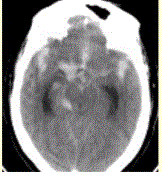

问题 患者男,50岁,突发昏迷、呕吐1h。查体:颈项强直,脑膜刺激征阳性,CT表现如图1。 有关动脉瘤,描述正确的是

选项 A.根据形态分为囊状、梭形、夹层及假性层动脉瘤 B.囊状15%发生于颅底willis环或椎基底动脉尖 C.梭形动脉瘤好发于颅底willis环 D.无血栓动脉瘤由于存在流空效应,在T1WI和T2WI上均为高信号 E.动脉瘤脑血管造影均为阳性

答案 A